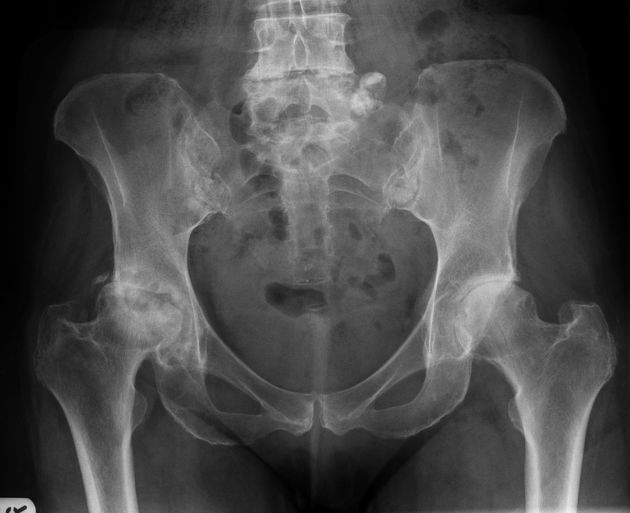

Example 3

Diagnosis

Osteoarthritis of the Hip (right)

Image 3: Feger, J., Niknejad, M. Osteoarthritis of the hip. Reference article, Radiopaedia.org. https://doi.org/10.53347/rID-81200